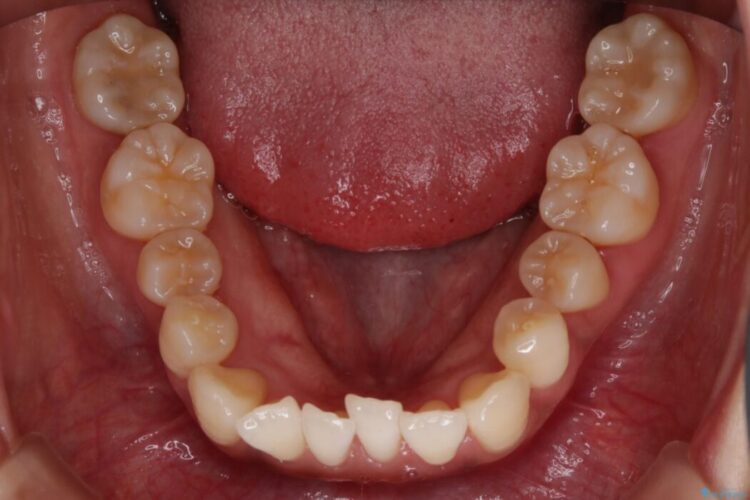

前歯のガタガタを気にされて来院されました。

検査の結果、骨の厚みに余裕がないことが判明しましたので、幅の拡大と歯の側面を削るIPRでは歯周病に対する不安を拭いきれないと判断しました。

よってマイクロインプラントを用い、奥歯から順番に遠心移動させることによってスペースを確保することにしました。